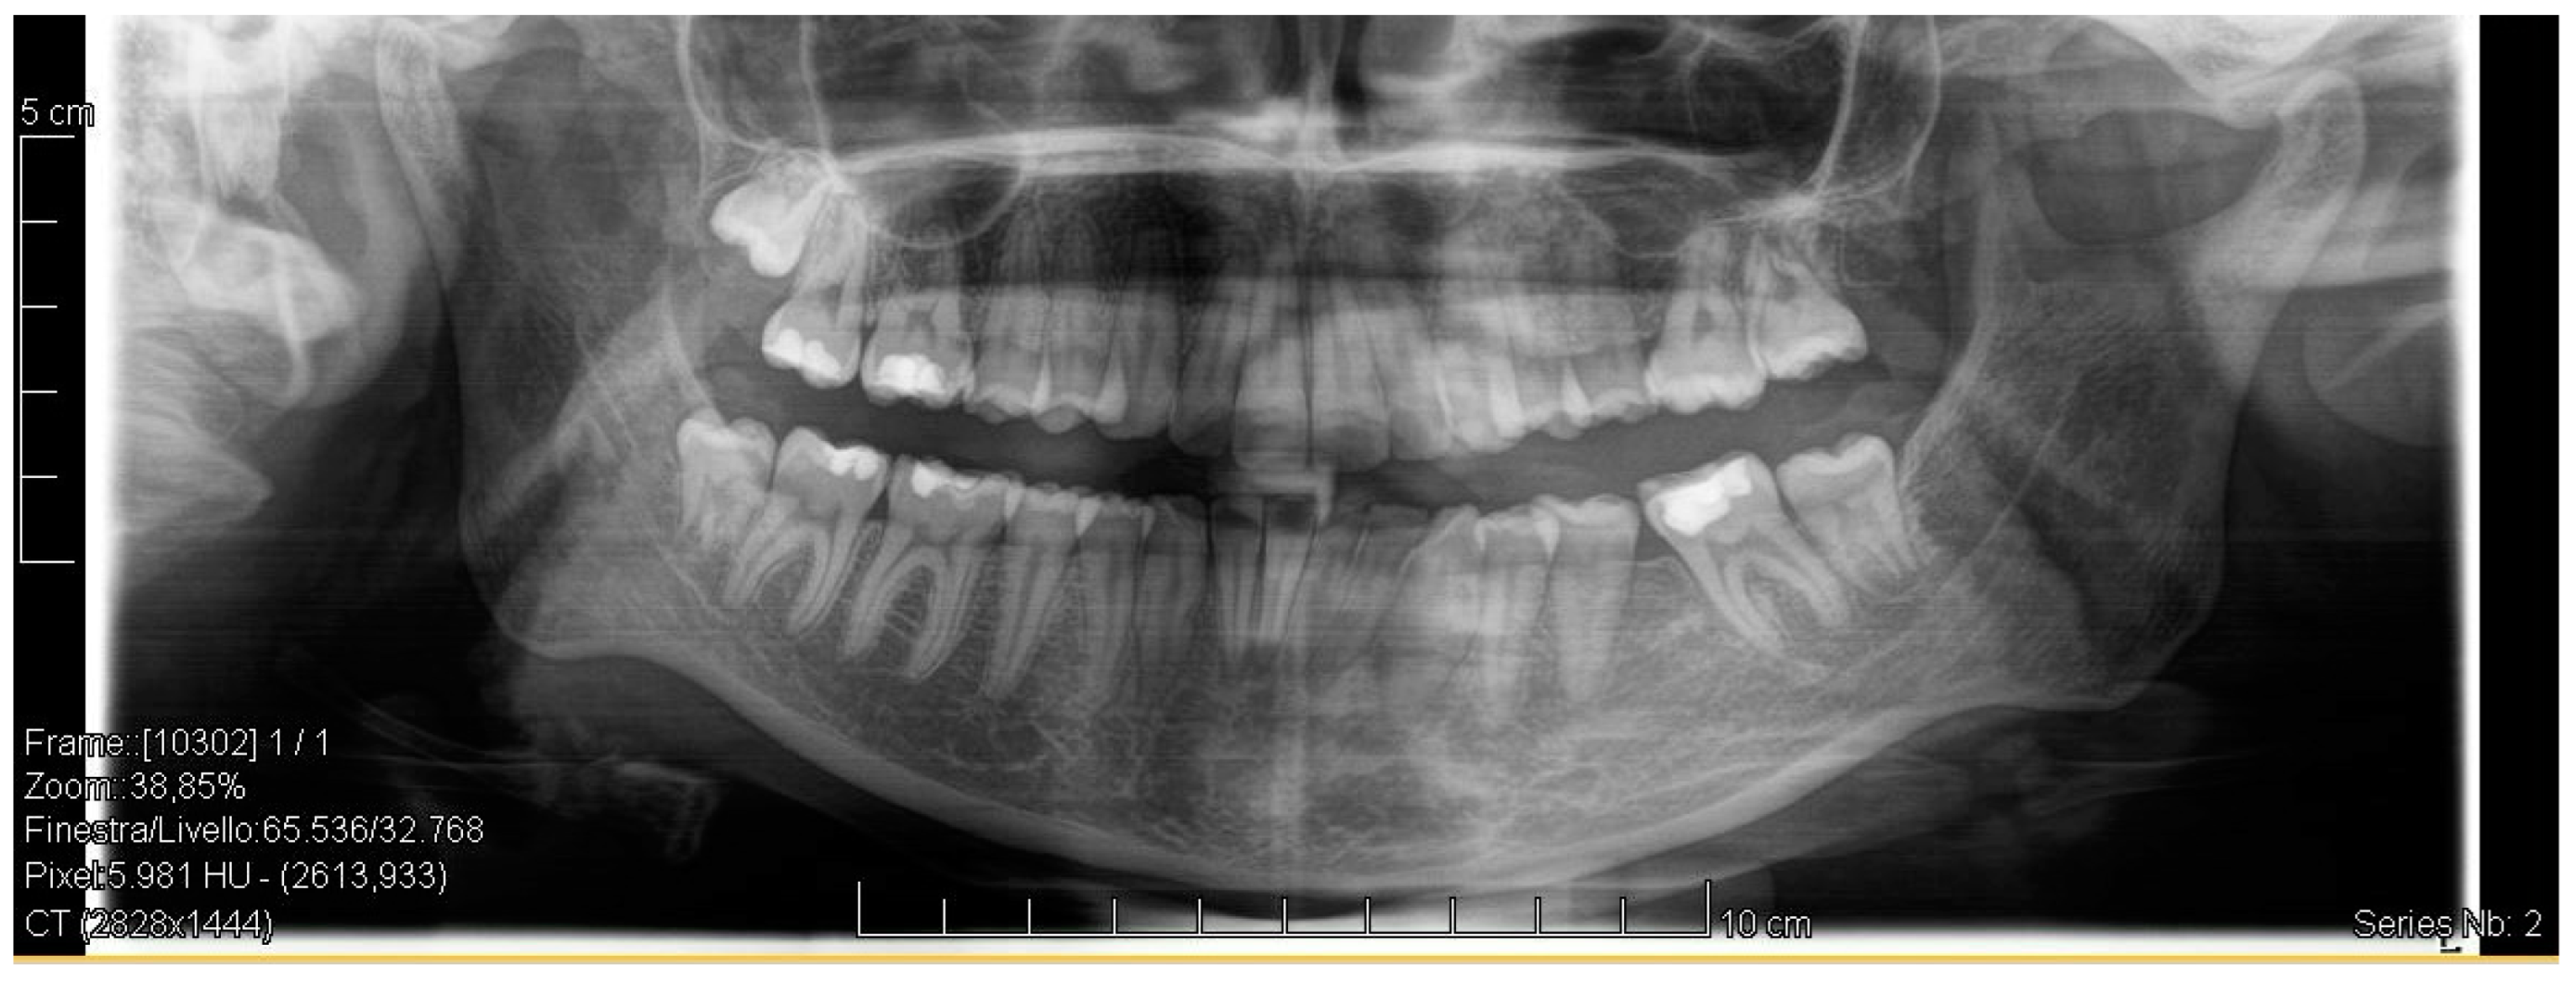

Figure 7.

Post-treatment radiograph showing extractive spaces’ closure.